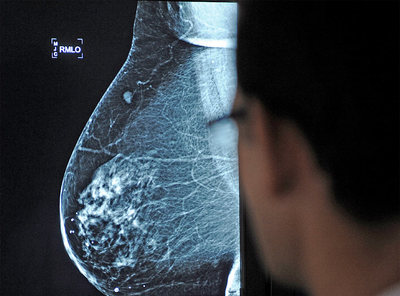

La propuesta de reducir las mamografías y citologías en EE UU desata el choque entre culturas médicas - Frente a la cantidad de pruebas, crece el número de científicos que demandan racionalidad

Aún hoy, en España cerca de una cuarta parte de las mujeres no visita al ginecólogo. El 75% sí que acude periódicamente. Muchas, para pasar por mamografías y citologías, ambas pruebas de cribado dirigidas a prevenir el cáncer de mama y de cérvix. Pero tanto el defecto como el exceso pueden acabar perjudicando la salud. En Estados Unidos, diferentes sociedades científicas han empezado a remover los cimientos del consumismo médico y han enfrentado dos culturas médicas: la que cree que cuantas más pruebas, mejor prevención, y la que opta por racionalizarlas, ya que el exceso también puede llevar a intervenciones perjudiciales.

El tema es peliagudo, porque no hay ninguna duda de que la introducción de la mamografía y la citología en la cartera sanitaria ha sido un gran logro que ha permitido disminuir la mortalidad en los dos tipos de cáncer que más afectan a las mujeres, el de mama (casi 6.000 muertes anuales en España) y el de cérvix (unas 600 muertes al año). Sin embargo, los estudios indican que no todas las mujeres se benefician igual. ¿Es necesario racionalizar estos dos tipos de cribado? Muchos expertos indican que sí. Por un lado, cada vez hay más evidencias científicas que muestran que sólo disminuyen la mortalidad cuando se realizan a la edad adecuada o cuando hay un riesgo incrementado por algún factor. Por otro, el afán de prevención puede llevar a realizar pruebas a mujeres demasiado jóvenes, en las que aún no existe un riesgo real. Y no sólo no se benefician de la prevención, sino que corren el riesgo de obtener diagnósticos inapropiados. No se trata de no hacer los cribados. Lo que muchos expertos plantean es la necesidad de racionalizarlos. ¿Cómo? Adaptando la edad y la frecuencia.